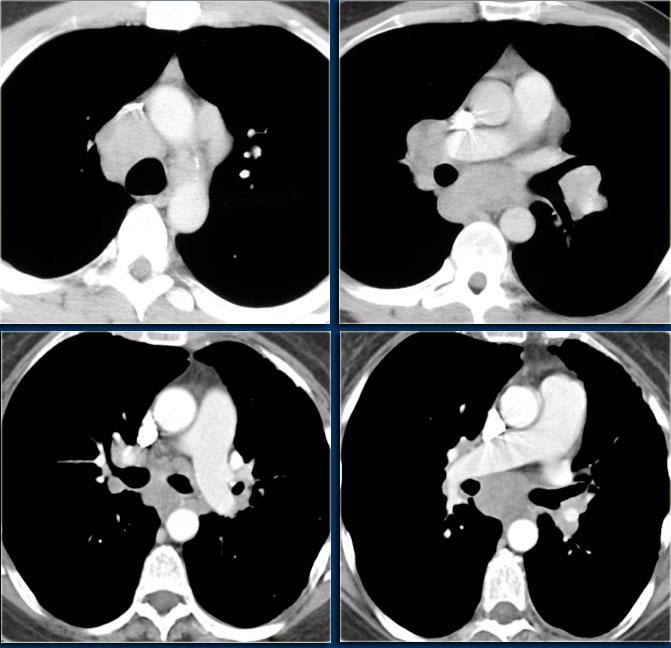

Trên CT, tăng sản biểu hiện là sự phì đại lan tỏa của tuyến ức, với sự bảo tồn hình dạng tam giác bình thường.

Định nghĩa tăng sản tuyến ức là thể tích tuyến ức tăng > 50%.

CT, MRI hoặc PET không thể phân biệt tăng sản phục hồi với thâm nhiễm tuyến ức do khối u.

Sự vắng mặt của các bệnh hoạt động khác và sự giảm dần kích thước tuyến ức trên các lần chụp CT nối tiếp hỗ trợ chẩn đoán tăng sản phục hồi.

Tuyến ức thường trở về kích thước bình thường trong 3 đến 6 tháng.